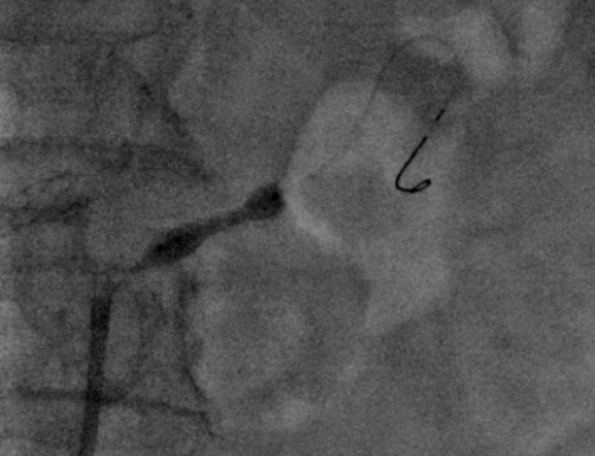

肾动脉CTA:双侧可见副肾动脉,双肾动脉起始部可见钙化斑块,双侧肾动脉及左侧副肾动脉近段重度狭窄。左髂总动脉夹层。

7F RDC配合4F Sim1导管选入左肾动脉,(4mm-20mm)Aviator Plus球囊尝试送入左肾动脉困难,更换(2mm-15mm)Gateway球囊后成功送入左肾动脉并完成预扩,植入(5mm-18mm)Palmaz Blue支架。